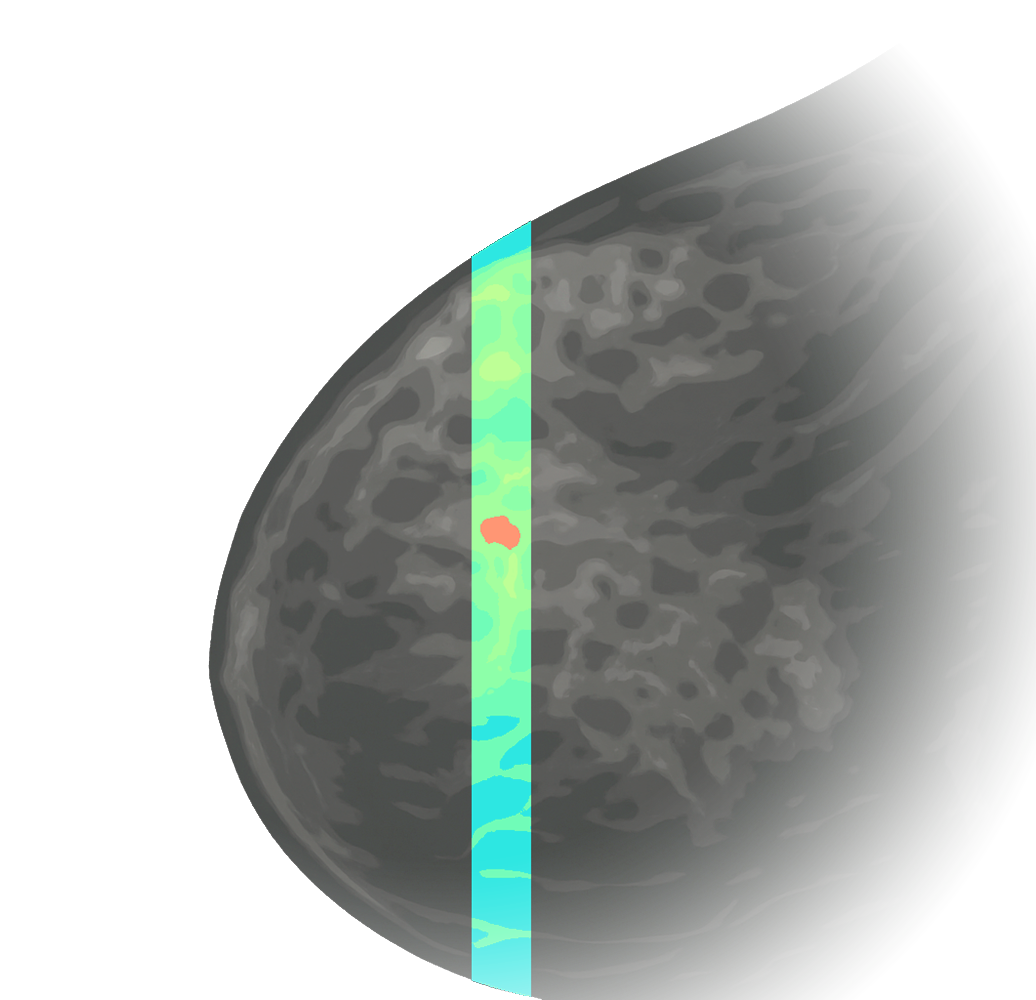

At Calidar, we are building next-generation X-ray diffraction imaging to reveal molecular-level signatures of disease. Our patented 4D Mammography technology measures these signatures from the breast noninvasively, providing a new dimension of data with the goal of earlier, more accurate diagnosis of breast cancer.

4D Mammography

Tissue Fingerprints

Maps X-ray scatter fingerprints linked to cancer.

Light-based 4D Mammography concept illustration